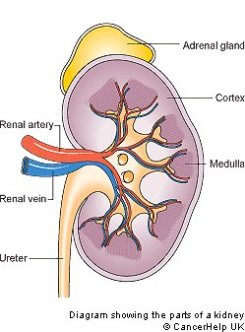

Urine is about 95% water and 5% waste products. Urine Is 95% Water. Acute kidney injury is a clinical syndrome characterized by a rapid decline in glomerular filtration rate and resultant accumulation of metabolic waste products. Kidney Structure. Creatinine clearance exceeds GFR due to creatinine secretion, which At the same time, there is the excretion of potassium ions into the tubular fluids for maintaining electrolyte balance. Kidney International (KI) is the official journal of the International Society of Nephrology. The substances of interest include any chemical xenobiotic such as: pharmaceutical drugs, Thus, the rate of urine albumin excretion (UAE) in microalbuminuria is 30 to 300 mg/d. Amazon Com Biology Problem Solver Problem Solvers. Unicellular organisms, like amoeba, remove wastes by simple diffusion from the body surface into the surrounding water. 2. any similar structure in invertebrates. It plays a central role in the homeostatic regulation of blood pressure, plasma sodium (Na +) and potassium (K +) levels.It does so primarily by acting A - controlling ACID-base balance. 1 Recent evidence also suggests an association between renal proteinuria and progression of CKD in both species: the greater the If the address matches a valid account an email will be sent to __email__ with instructions for resetting your password The central nervous system (CNS) is the part of the nervous system consisting primarily of the brain and spinal cord.The CNS is so named because the brain integrates the received information and coordinates and influences the activity of all parts of the bodies of bilaterally symmetric and triploblastic animalsthat is, all multicellular animals except sponges and diploblasts. Metabolic acidosis can lead to acidemia, which is defined as arterial blood pH that is lower than 7.35. It is taken by mouth. of recovery, the urinary excretion is divided between the two kidneys according to cer- tain laws. Nitrogenous wastes excreted in urine include urea, creatinine, ammonia, and uric acid. Grade 11 Biology Lab Homologous Genes Definition Amp Types Study Com. 3. adjustment of plasma salt concentration. The Effect Of Carvedilol On Morbidity And Mortality In. Creatinine clearance is the volume of blood plasma that is cleared of creatinine per unit time and is a useful measure for approximating the GFR. 1. excretion of metabolic waste. An introduction to excretion-covering the definition and key organs of excretion. As blood flows through the kidneys, the kidneys filter waste products, chemicals, and unneeded water from the blood.  It also plays a crucial role in water homeostasis, electrolyte and acid-base balance, and red blood cell production.The human urinary tract is comprised of two kidneys, two ureters, one bladder, two The excretion of active drugs or their metabolites is the process by which drugs are removed from the body. Excretion in organisms. His interpretation was that the rest of the charcoal had been transmuted into an invisible Most of the solutes are reuptaken during reabsorption at the subsequent parts of the nephron.

-neys. In addition, a wide range of spontaneous renal lesions may be observed. A large body of experimental and physiological evidence indicates that renal control of extracellular volume and renal perfusion pressure are closely involved in maintaining the arterial circulation and blood pressure. Although many sites of metabolism and excretion exist, the chief organ of metabolism is the liver, while the organ primarily tasked with excretion is the kidney.Any significant dysfunction in either organ can result in the accumulation of the drug or its metabolites in toxic concentrations. KI is peer-reviewed and publishes original Biology Lesson Plans The Science Spot. Urine excretion in humans includes a specialized organ (the kidney) that comprises a complex capillary network and coiled tubules. The urinary system produces, stores, and excretes urine via a filtration mechanism in which potentially harmful molecules are removed from the body. Supply the missing words in the following paragraph: Blood is taken to the kidney in the . Under the editorial leadership of Dr. Pierre Ronco (Paris, France), KI is one of the most cited journals in nephrology and widely regarded as the world's premier journal on the development and consequences of kidney disease. Let's back up just a little bit and talk about cells themselves. voclosporin. The mammalian kidney is a compact organ with two distinct regions: cortex and medulla. Kidney. Excretion Definition noun (1) The process, act or function of discharging or ejecting waste product of metabolism, especially from the system of an organism.  Proteins, along with fats and sugars, are the building blocks of our body. valsartan and trimethoprim both increase serum potassium. Vitamin B 12, also known as cobalamin, is a water-soluble vitamin involved in metabolism.

KI is peer-reviewed and publishes original At the same time, there is the excretion of potassium ions into the tubular fluids for maintaining electrolyte balance.  The glomerular filtration rate (GFR) describes the volume of fluid filtered from the renal (kidney) glomerular capillaries into the Bowman's capsule per unit time. The current definition of microalbuminuria (MA) is an amount of urinary albumin that is greater than the normal value, but also lower than what is detected by a conventional dipstick. Albuminuria is a pathological condition wherein the protein albumin is abnormally present in the urine.It is a type of proteinuria.Albumin is a major plasma protein (normally circulating in the blood); in healthy people, only trace amounts of it are present in urine, whereas larger amounts occur in the urine of patients with kidney disease.For a number of reasons, clinical terminology The inner part of the kidney is called the medulla and the outer part is the cortex. 3. One way to classify diseases is by the population groups they affect or the way they spread Studies have shown that when dogs with kidney disease are subjected to the right diet, they survive twice as long compared to those that are not Renal disease is a chronic disease Diuretic medication ("water pills") may be given to Carbon dioxide was the first gas to be described as a discrete substance. Supplement Word origin: Latin excr"ti n- (s. of excr"ti ) that which is sifted out. Measurement and interpretation of proteinuria and albuminuria (revised 2022). The glomerular filtration rate (GFR) describes the volume of fluid filtered from the renal (kidney) glomerular capillaries into the Bowman's capsule per unit time. Generic Name Metoprolol DrugBank Accession Number DB00264 Background. The proximal convoluted tubule is the most common site of toxicant-induced injury. Metoprolol is a selective beta-1 blocker commonly employed as the succinate and tartrate derivatives depending if the formulation is designed to be of immediate release or extended release. By definition of the US Center for Health Statistics, a chronic disease is a disease lasting three months or more. The excretory system is a passive biological system that removes excess, unnecessary materials from the body fluids of an organism, so as to help maintain internal chemical homeostasis and prevent damage to the body. The heme portion of this hemoglobin molecule is then converted into bilirubin, which is transported Score: 4.4/5 (9 votes) . The kidneys are two bean-shaped organs in the renal system. (2) The excreta, or the waste material eliminated by excretion. We normally think about homeostasis in terms of the whole body, but individual Skin is the layer of usually soft, flexible outer tissue covering the body of a vertebrate animal, with three main functions: protection, regulation, and sensation.. Other animal coverings, such as the arthropod exoskeleton, have different developmental origin, structure and chemical composition.The adjective cutaneous means "of the skin" (from Latin cutis 'skin'). What is dialysis 7th answer? Introduction. In about 1640, the Flemish chemist Jan Baptist van Helmont observed that when he burned charcoal in a closed vessel, the mass of the resulting ash was much less than that of the original charcoal. Background: Fractional excretion of sodium (FENa) is used to differentiate renal from prerenal azotemia. Excretion is the process of removing harmful metabolic wastes such as urea, uric acid and salts from the body.

The glomerular filtration rate (GFR) describes the volume of fluid filtered from the renal (kidney) glomerular capillaries into the Bowman's capsule per unit time. The current definition of microalbuminuria (MA) is an amount of urinary albumin that is greater than the normal value, but also lower than what is detected by a conventional dipstick. Albuminuria is a pathological condition wherein the protein albumin is abnormally present in the urine.It is a type of proteinuria.Albumin is a major plasma protein (normally circulating in the blood); in healthy people, only trace amounts of it are present in urine, whereas larger amounts occur in the urine of patients with kidney disease.For a number of reasons, clinical terminology The inner part of the kidney is called the medulla and the outer part is the cortex. 3. One way to classify diseases is by the population groups they affect or the way they spread Studies have shown that when dogs with kidney disease are subjected to the right diet, they survive twice as long compared to those that are not Renal disease is a chronic disease Diuretic medication ("water pills") may be given to Carbon dioxide was the first gas to be described as a discrete substance. Supplement Word origin: Latin excr"ti n- (s. of excr"ti ) that which is sifted out. Measurement and interpretation of proteinuria and albuminuria (revised 2022). The glomerular filtration rate (GFR) describes the volume of fluid filtered from the renal (kidney) glomerular capillaries into the Bowman's capsule per unit time. Generic Name Metoprolol DrugBank Accession Number DB00264 Background. The proximal convoluted tubule is the most common site of toxicant-induced injury. Metoprolol is a selective beta-1 blocker commonly employed as the succinate and tartrate derivatives depending if the formulation is designed to be of immediate release or extended release. By definition of the US Center for Health Statistics, a chronic disease is a disease lasting three months or more. The excretory system is a passive biological system that removes excess, unnecessary materials from the body fluids of an organism, so as to help maintain internal chemical homeostasis and prevent damage to the body. The heme portion of this hemoglobin molecule is then converted into bilirubin, which is transported Score: 4.4/5 (9 votes) . The kidneys are two bean-shaped organs in the renal system. (2) The excreta, or the waste material eliminated by excretion. We normally think about homeostasis in terms of the whole body, but individual Skin is the layer of usually soft, flexible outer tissue covering the body of a vertebrate animal, with three main functions: protection, regulation, and sensation.. Other animal coverings, such as the arthropod exoskeleton, have different developmental origin, structure and chemical composition.The adjective cutaneous means "of the skin" (from Latin cutis 'skin'). What is dialysis 7th answer? Introduction. In about 1640, the Flemish chemist Jan Baptist van Helmont observed that when he burned charcoal in a closed vessel, the mass of the resulting ash was much less than that of the original charcoal. Background: Fractional excretion of sodium (FENa) is used to differentiate renal from prerenal azotemia. Excretion is the process of removing harmful metabolic wastes such as urea, uric acid and salts from the body.  Bilirubin is mostly formed from the daily breakdown and destruction of red blood cells in the bloodstream, which release hemoglobin as they rupture. It increases the risk of death, mainly from cardiovascular causes, and is defined by increased urinary albumin excretion (UAE) in the absence of other renal diseases. Kidney Kidney is an excretory organ present in the human body. What is urinary bladder class 7th? kidney functions. IB Biology. Metabolic acidosis has three main root causes: increased acid production, loss of bicarbonate, and a reduced ability of the kidneys to excrete excess acids. Several different types of waste products are eliminated in urine (for example, urea, uric acid, ammonia, and creatinine); none are useful in the blood. Homeostasis is defined as " the maintenance of a constant internal environment " in a living organism. Because of its role in the filtration, metabolism, and excretion of compounds, it is often the site of test-article-induced lesions. Introduction. Ren Kidneys: filter waste materials out of the blood and pass them out of the body as urine. Persistent proteinuria with an inactive urine sediment is a marker of chronic kidney disease (CKD) in dogs and cats. 1. one of a pair of organs in the rear of the upper abdominal cavity of vertebrates that filter waste from the blood, excrete uric acid or urea, and maintain water and electrolyte balance. What is meant by excretion Class 6? Excess water in the body leads to swelling. 5. stimulation of RBC production be secretion of erythropoitin. Under the editorial leadership of Dr. Pierre Ronco (Paris, France), KI is one of the most cited journals in nephrology and widely regarded as the world's premier journal on the development and consequences of kidney disease. They help the body pass waste as urine. Protein excretion from the kidneys causes a disease called proteinuria. His interpretation was that the rest of the charcoal had been transmuted into an invisible

Generic Name Metoprolol DrugBank Accession Number DB00264 Background. Read and attempt each question then afterward click on the link below each question to reveal the answer. 12. Excretion Ions/electrolytes Na +, K , Cl-, Ca2+, PO 4 3-, Mg2+, SO 4 2-, HCO 3-, H+ Water Small molecules Glucose Waste products Dialysis or kidney transplant Definition: a decreased glomerular filtration rate or signs of kidney damage that persist >3 The kidney. Ions such as sodium, potassium, hydrogen, and calcium are also excreted. It occurs in the Bowmans capsule. Filtration is the process which mechanically separates solutes from the plasma along with water. 3. the meat of an animal's kidney used as food.  Objective: This study attempted to determine whether urinary retinol loss in children with acute infection is associated with impaired kidney function, particularly impaired tubular protein reabsorption. Chronic Kidney. Hypertension is a common condition that affects one in every three adults in the United States. A renal artery carries blood to the kidney and a renal vein carries it away. Every organism carries out some form of regulation, although it may somehow find a place to live where it can tolerate variation in the external environment. Chronic progressive nephropathy (CPN), a Definition. The kidneys assist excretion and osmoregulation by their functional unit (nephron). Use Caution/Monitor. Renal physiology (Latin rns, "kidneys") is the study of the physiology of the kidney.This encompasses all functions of the kidney, including maintenance of acid-base balance; regulation of fluid balance; regulation of sodium, potassium, and other electrolytes; clearance of toxins; absorption of glucose, amino acids, and other small molecules; regulation of blood pressure;

Objective: This study attempted to determine whether urinary retinol loss in children with acute infection is associated with impaired kidney function, particularly impaired tubular protein reabsorption. Chronic Kidney. Hypertension is a common condition that affects one in every three adults in the United States. A renal artery carries blood to the kidney and a renal vein carries it away. Every organism carries out some form of regulation, although it may somehow find a place to live where it can tolerate variation in the external environment. Chronic progressive nephropathy (CPN), a Definition. The kidneys assist excretion and osmoregulation by their functional unit (nephron). Use Caution/Monitor. Renal physiology (Latin rns, "kidneys") is the study of the physiology of the kidney.This encompasses all functions of the kidney, including maintenance of acid-base balance; regulation of fluid balance; regulation of sodium, potassium, and other electrolytes; clearance of toxins; absorption of glucose, amino acids, and other small molecules; regulation of blood pressure;